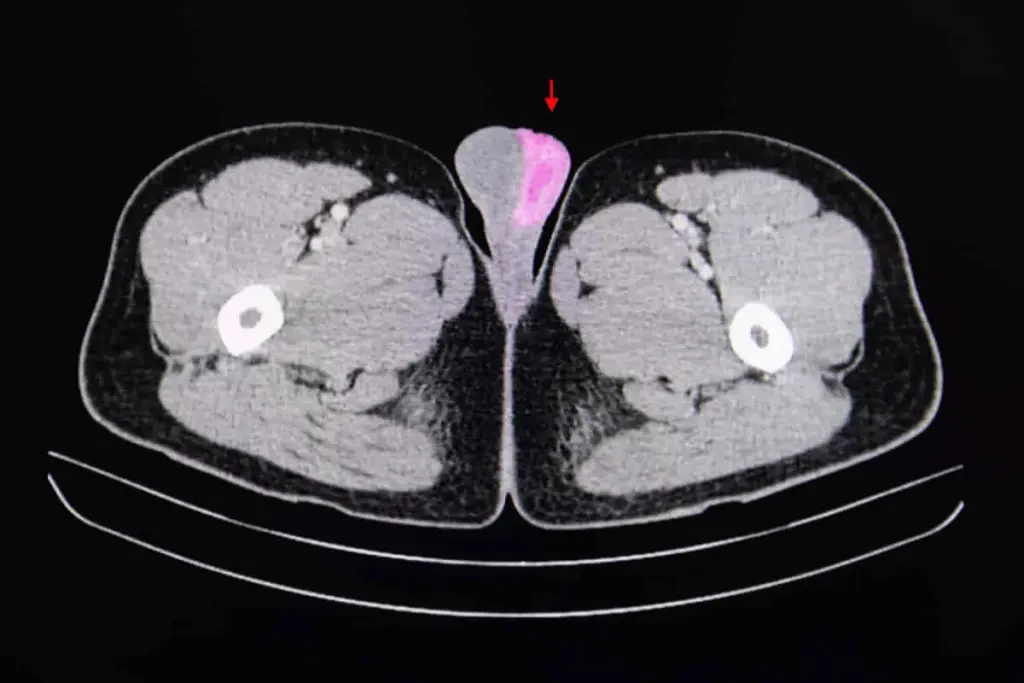

Several tests stage testicular cancer:

- Imaging tests like CT and PET scans to see cancer spread.

- Blood tests for tumor markers like alpha-fetoprotein and hCG.

- Surgical exploration to check lymph nodes in the abdomen.

These tests give important info for a good treatment plan.

Imaging tests are key in finding testicular cancer. Ultrasound is often used. It can tell if a mass is solid or filled with fluid. This info is vital for treatment planning.

Computed tomography (CT) scans might also be used. They check if cancer has spread. This helps decide on the best treatment.